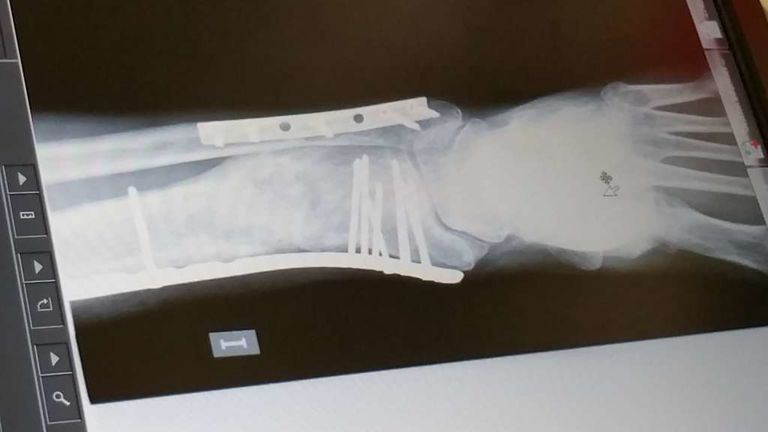

jerolo Publicado 17 de Marzo del 2016 Autor Compartir Publicado 17 de Marzo del 2016 Bueno,al fin consolidó,2 años y medio llorando_ me quedo más cojo de lo que pensaba,pues me tendrè que joder, no me queda otra,aùn ando con el puto bastòn....ahi van las placas Enlace al comentario Compartir en otros sitios web More sharing options...

jerolo Publicado 30 de Mayo del 2016 Autor Compartir Publicado 30 de Mayo del 2016 Ya no sé si tomarlo de coña o suIcidarme.....me fuí a urgencias porque no aguantaba el puto dolor y......6ª OPERACIÓN!!!!!!!!!!! para retirar las placas,o sea muletas otra vez y ahora que viene el veranito moto en el garaje,de puta madre.Por cierto,llevo 2 AÑOS y 8 MESES.espero que no le pase a nadie lo mismo Enlace al comentario Compartir en otros sitios web More sharing options...

jerolo Publicado 17 de Julio del 2016 Autor Compartir Publicado 17 de Julio del 2016 ¿Cómo va lo tuyo, Gerardo?? Ahora puedo decir que sí que estoy mejorando,me opera por 6°vez me sacaron las placas y mejoró rápido,aún ando con bastón pero en breve lo dejaré pero me quedo cojo;en septiembre 3AÑOS!!!!!no le deso a nadie que le pase lo mismo. Gracias por tu interés amigo trato_hecho Enlace al comentario Compartir en otros sitios web More sharing options...